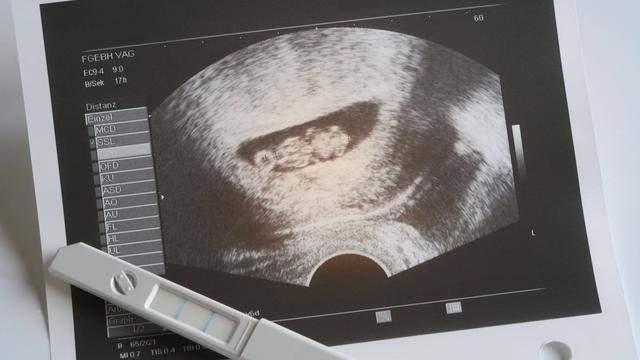

Der Herzschlag des Babys kann in der Regel zwischen der 6. und 8. Schwangerschaftswoche auf dem Ultraschallgerät erkennbar sein. Bei einem Frauenarzttermin in der 6. Schwangerschaftswoche besteht eine gute Chance, den Herzschlag zu sehen. Allerdings hängt dies von verschiedenen Faktoren ab, wie zum Beispiel der Position des Embryos in der Gebärmutter und der Qualität des Ultraschallgeräts.

Es ist jedoch wichtig zu beachten, dass selbst wenn der Herzschlag noch nicht sichtbar ist, dies kein Grund zur Sorge ist. Spätestens bis zur 8. Schwangerschaftswoche sollte der Herzschlag deutlich erkennbar sein.

Bei einer Ultraschalluntersuchung in dieser Zeit wird Ihr Frauenarzt wahrscheinlich die Fruchthöhle und den Dottersack sehen können. Der Dottersack spielt eine wichtige Rolle bei der Blutbildung und übernimmt vorübergehend wichtige Stoffwechselfunktionen.

Der Herzschlag eines Babys ist in der Regel zwischen der 6. und 8. Schwangerschaftswoche auf dem Ultraschall erkennbar. Es kann jedoch auch von verschiedenen Faktoren abhängen, wie zum Beispiel der Position des Embryos in der Gebärmutter und der Qualität des Ultraschallgeräts.

Bei einem Frauenarzttermin in der 6. Schwangerschaftswoche wird normalerweise die Fruchthöhle und der Dottersack sichtbar sein. Der Dottersack ist für die Blutbildung zuständig und übernimmt vorübergehend wichtige Stoffwechselfunktionen.

Obwohl der Herzschlag möglicherweise noch nicht sichtbar ist, braucht man sich keine Sorgen zu machen. Spätestens in der 8. Schwangerschaftswoche sollte er erkennbar sein. Der Frauenarzt wird auch andere Untersuchungen durchführen, wie zum Beispiel eine Blutdruckmessung, eine Urinuntersuchung und die Ermittlung des Körpergewichts.

Bestimmt fragt ihr euch, ab welchem Zeitpunkt ihr das Herz auf dem Ultraschallgerät schlagen sehen könnt. In der Regel könnt ihr den Herzschlag eures Kindes zwischen der 6. und der 8. Schwangerschaftswoche auf dem Ultraschallgerät erkennen.

Zwar kann der Herzschlag des Embryos bereits gegen Ende der 6. Schwangerschaftswoche zu erkennen sein, doch auch wenn euer Frauenarzt das Herz auf dem Ultraschall noch nicht pochen sieht, braucht ihr euch keine Sorgen zu machen. Spätestens in der 8. Schwangerschaftswoche ist der Herzschlag erkennbar. Ob der Herzschlag bereits in der 6. Schwangerschaftswoche zu erkennen ist, hängt unter anderem davon ab, welche Position der Embryo in eurer Gebärmutter eingenommen hat und natürlich auch von der Qualität des Ultraschallgeräts sowie der Entwicklung des Embryos.

Was der Frauenarzt jedoch mit großer Gewissheit sehen wird, ist die Fruchthöhle, welche sich in der Gebärmutter gebildet hat, und den Dottersack. Der Dottersack ist verantwortlich für die Blutbildung und übernimmt vorerst die wichtigen Stoffwechselfunktionen.